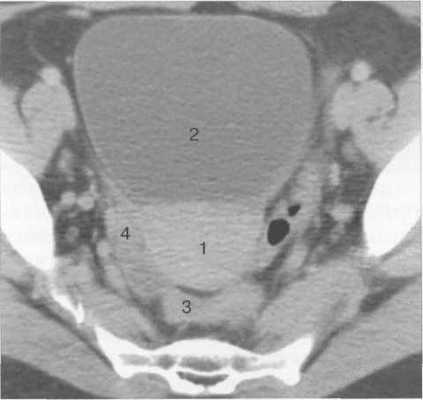

Матка занимает центральное положение в полости малого таза. Тело матки при КТ имеет овальную форму, однородную структуру, четкие контуры. Кпереди от матки располагается мочевой пузырь (рис. 15.6). Длина (высота) матки и ее поперечный размер меняются в зависимости от степени наклона кпереди, заполнения мочевого пузыря и прямой кишки. Переднезад-ний размер матки не превышает 50 мм. При резком загибе кпереди наблюдается деформация задней стенки мочевого пузыря. Денсито-метрическая плотность матки составляет 40— 60 HU. Широкие связки матки четко не диффе-

Рис. 15.6. КТ нормального строения тела матки.

Здесь и на рис. 15.7, 15.8:

1 — матка; 2 — мочевой пузырь; 3 — прямая кишка;

ренцируются. Иногда возможна визуализация ее круглых связок, которые определяются в виде тонких линейных структур, идущих от боковых поверхностей дна матки к стенкам таза. Кзади от круглых связок располагаются яичники. На КТ- срезах яичники отображаются в виде однородных образований плотностью 20—30 HU. Их визуализация зависит от фазы менструального цикла, величины яичников и возраста женщины (в менопаузе и препубертатном периоде их визуализация затруднена).